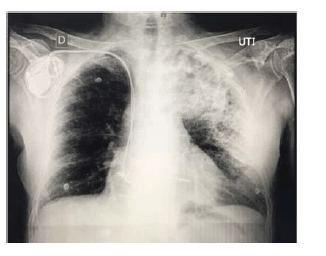

Considere um paciente de 66 anos de idade, com histórico de hipertensão arterial e diabetes controlados, além de ser cardiopata com marcapasso artificial. Relata calafrios com dois dias de evolução e tosse produtiva, além de estar taquipneico, com FR = 32 ipm, com PA = 110 mmHg x 82 mmHg; e com pulso = 126 bpm. Refere cansaço com dispneia. Tem nível de consciência preservado, com SatO2 = 89% (ar ambiente) e ureia = 58 mg/dL (VR = 5 mg/dL – 40 mg/dL). Apresenta o exame de raios X de tórax mostrado e nega internação ou uso de antibióticos no último ano.